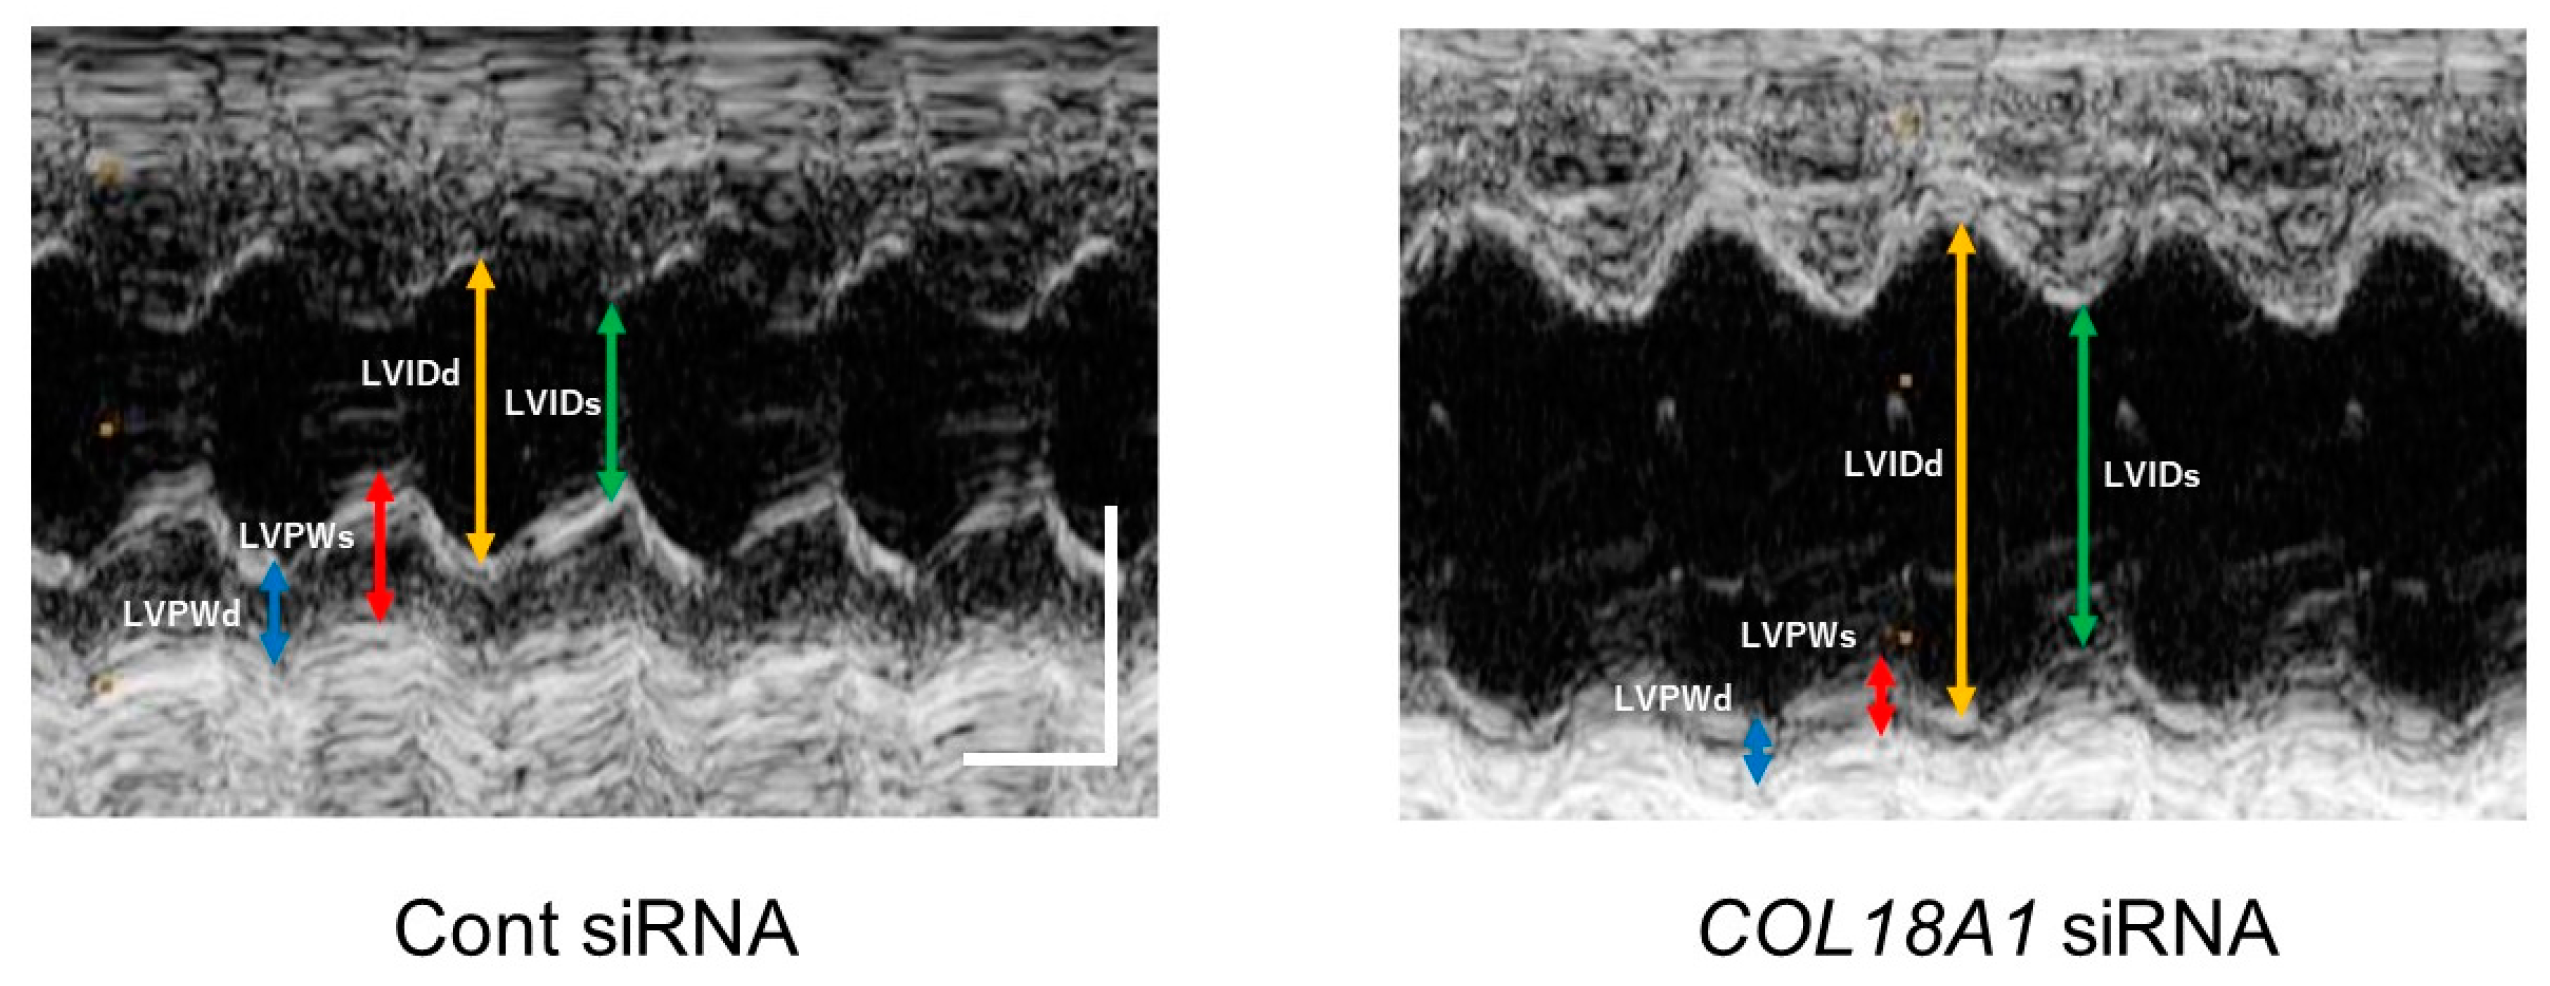

In the echocardiographic analysis, left ventricular (LV) mass was not changed by a COL18A1 siRNA injection. On the other hand, LV internal dimension at end-systole (LVIDs) (n = 6, p < 0.01), interventricular septum (IVS)/LV posterior wall (LVPW) (n = 6, p < 0.05) and end-systolic volume (ESV) (n = 6, p < 0.05) were increased by a COL18A1 siRNA injection. In addition, LVPW at end-diastole (LVPWd) (n = 6, p < 0.01), end-systole (LVPWs) (n = 6, p < 0.01) and percentage LVPW thickness (LVPW%) (n = 6, p < 0.05) were decreased by a COL18A1 siRNA injection. These observations demonstrated that the endostatin knockdown induced thinning and dilatation of LV. The decrease of fractional shortening (FS) (n = 6, p < 0.01) and ejection fraction (EF) (n = 6, p < 0.01) indicated that the endostatin knockdown worsened the cardiac function (Figure 5 and Table 2).

It has been reported that endostatin expression increased in the infarcted area of rat myocardial infarction model [27,28]. Therefore, we examined the effect of endostatin knockdown by COL18A1 siRNA on the remodeling of infarcted area. Interestingly, a knockdown of COL18A1 gene caused a remarkable thinning of the infarcted area, which was characterized by the decrease of LVPWd, LVPWs, and LVPW% and the increase of LVIDs, IVS/LVPW, and ESV (Figure 5 and Table 2). The endostatin knockdown also worsened cardiac function, which was characterized by the decrease of FS and EF (Figure 5 and Table 2). In addition, the α-SMA-positive myofibroblasts in the infarcted area of the COL18A1 siRNA-injected rats appeared sparse compared with control siRNA-injected rats (Figure 6). The insufficient proliferation and migration of myofibroblasts after myocardial infarction is thought to induce thinning of the wall, cardiac dilatation, cardiac dysfunction, and ventricular wall rupture [46]. Furthermore, scar thickness in the infarcted area of COL18A1 siRNA-injected rats were decreased compared with control siRNA-injected rats (Figure 7). Therefore, it is suggested that endostatin is necessary for the sufficient proliferation and migration of myofibroblasts in the infarcted area, which contributes to the scar formation. The limitation of this study is that we used a COL18A1 siRNA to knockdown endostatin. Further study is needed to investigate the influence of COL18A1-specific gene knockdown on the healing process after myocardial infarction.

Figure 5. The M-mode echocardiographic image from parasternal short axis view of the left ventricle at the level of papillary muscles in siRNA-injected myocardial infarction model rats. After the ligation of the left anterior descending artery (LAD) in rats, sixteen μg of COL18A1 siRNA or Cont siRNA was injected into the infarcted myocardium. Two weeks after the operation, echocardiography was performed. Representative images of M-mode on the parasternal short axis view of the left ventricle are shown (Cont siRNA: n = 6, COL18A1 siRNA: n = 6). Scale bar: 100 msec (horizontal) and 5 mm (vertical). LVIDd: left ventricular internal dimension at end-diastole, LVIDs: Left ventricular internal dimension at end-systole, LVPWd: Left ventricular posterior wall at end-diastole, LVPWs: Left ventricular posterior wall at end-systole.